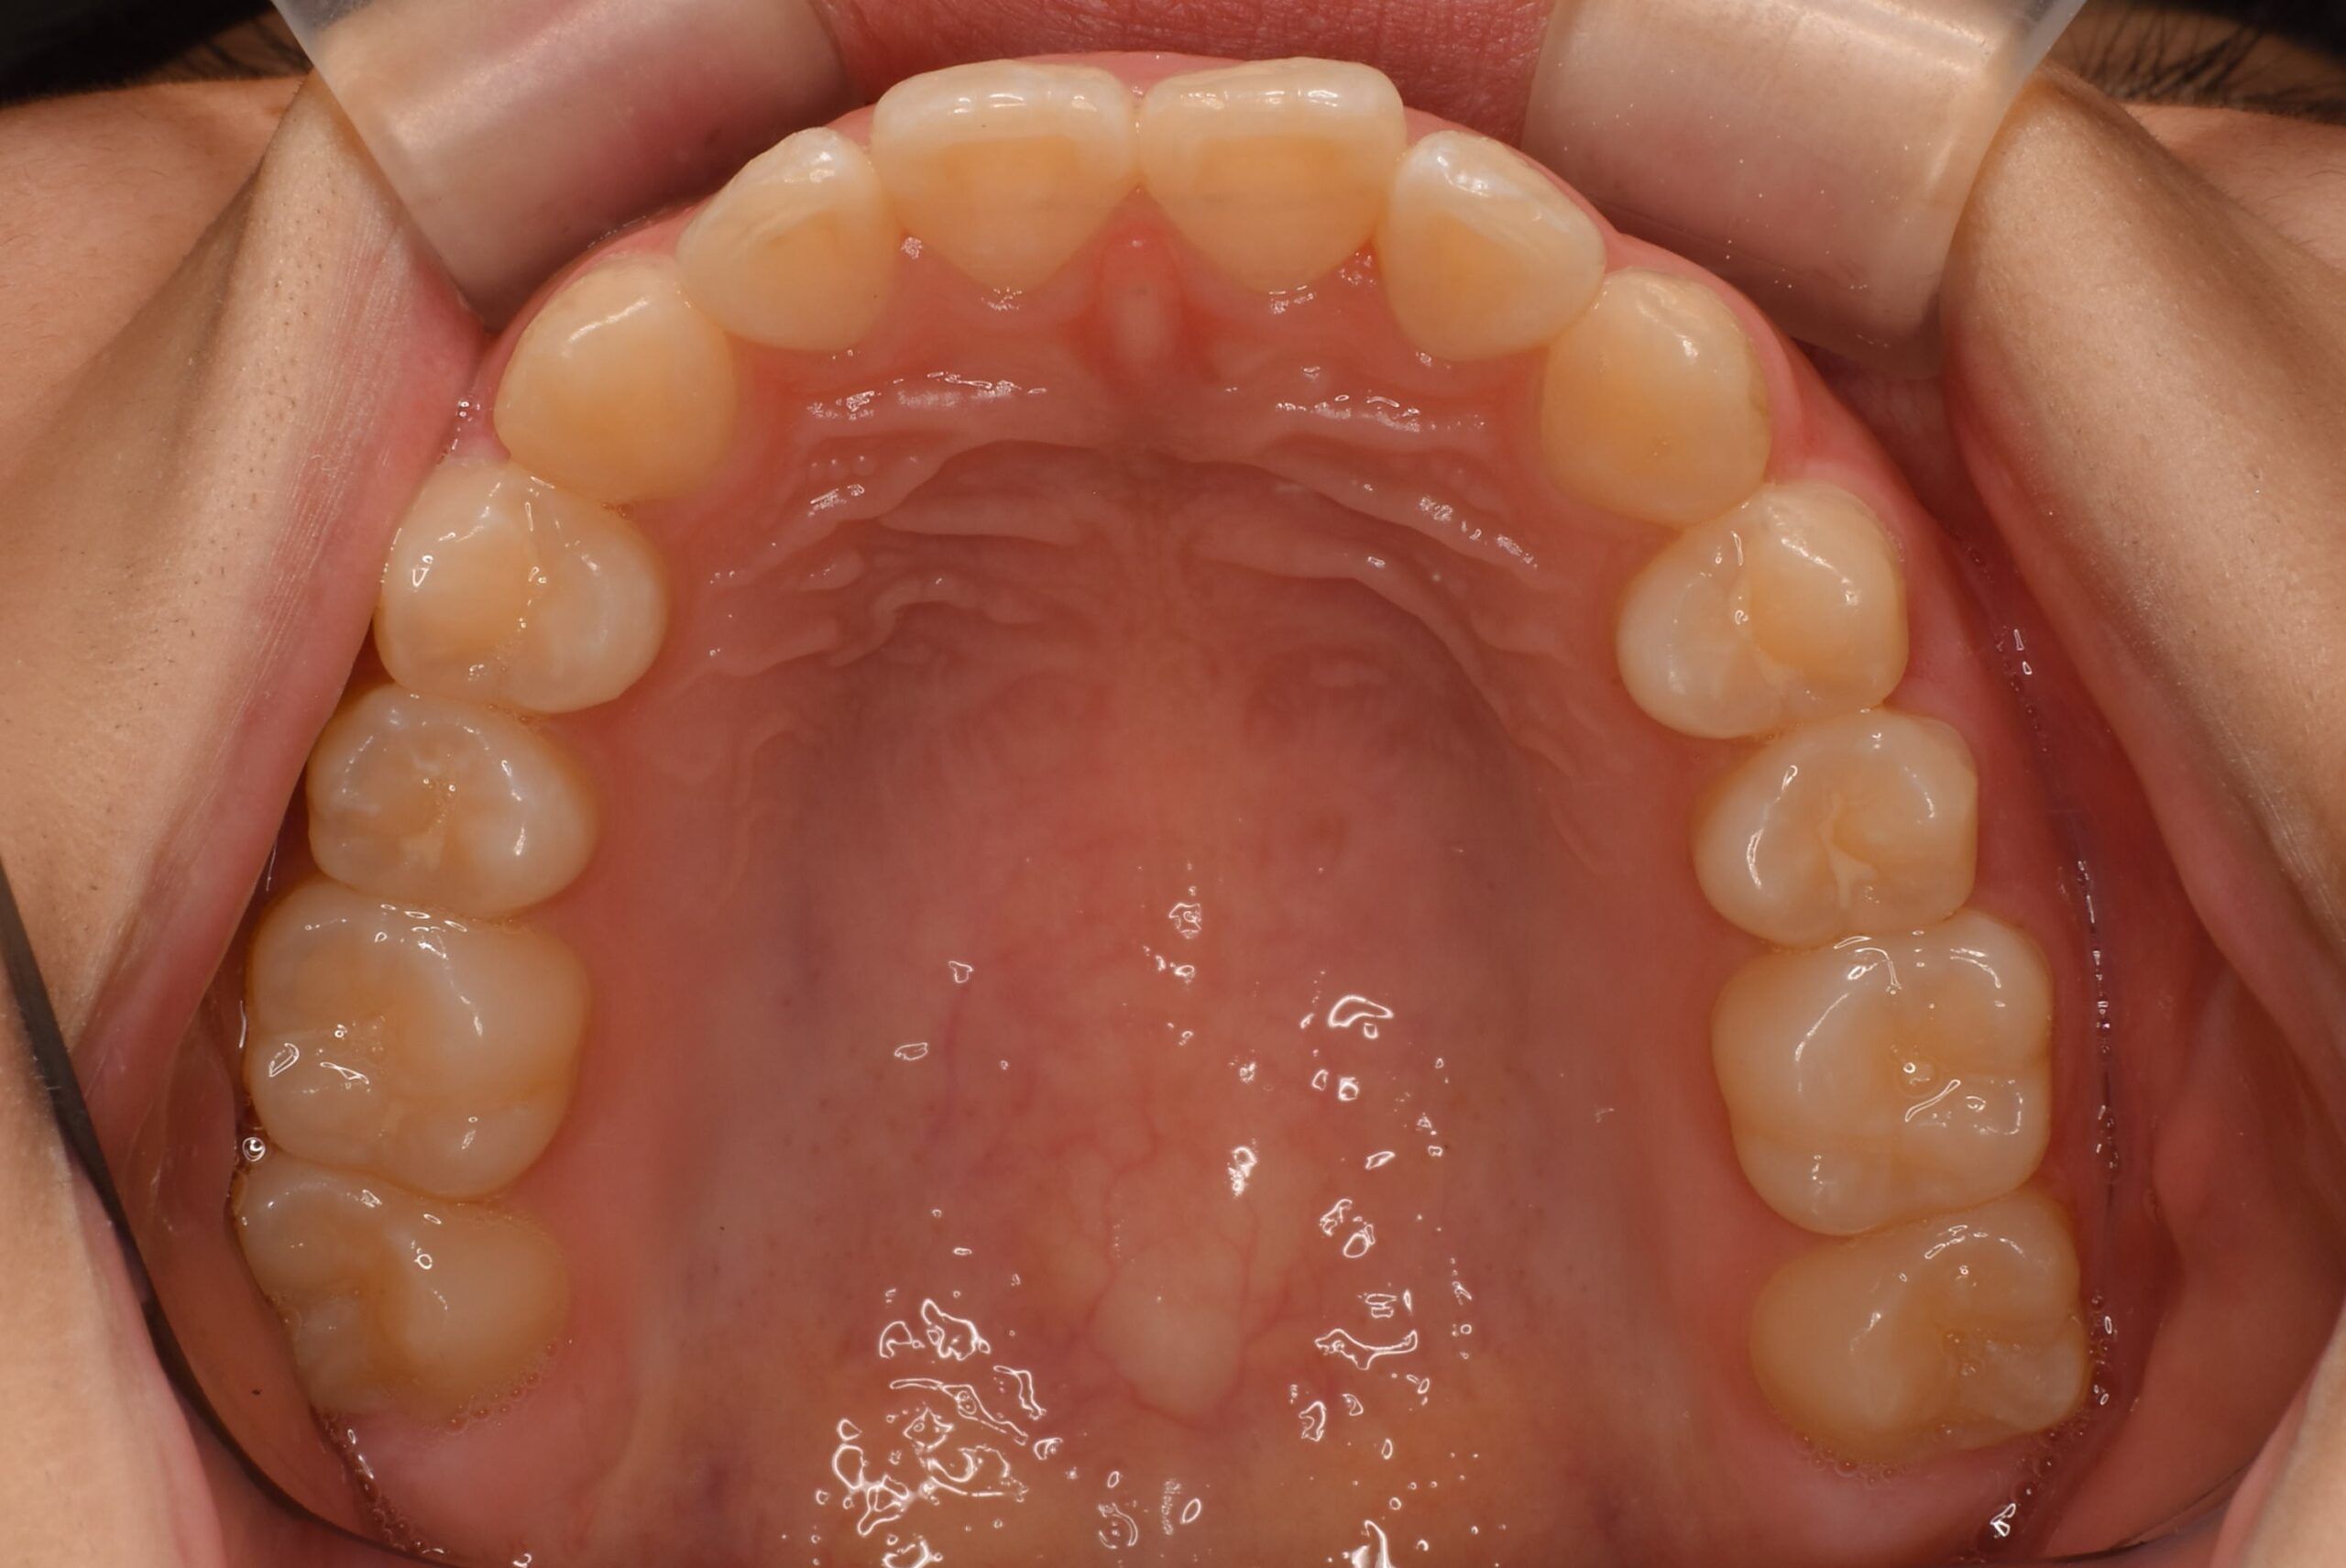

• 治療後_上顎咬合面

歯列全体を整えることで、叢生(歯のガタつき)の改善と咬合のバランス回復を図りました。

必要に応じて、IPR(歯と歯の間をわずかに削る処置)でスペースを確保し、歯の移動をスムーズに進めました。